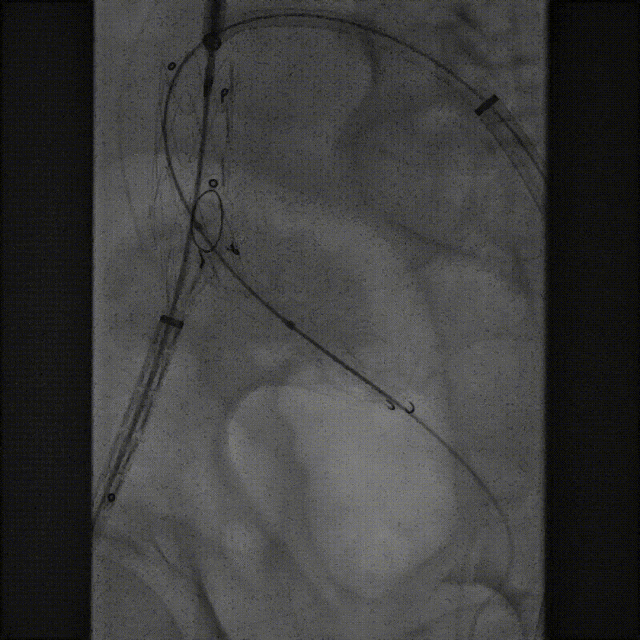

该技术主要适用于采用旋转式释放机制的支架。其核心操作步骤为:在主体支架释放出前2-3节后,轻微松开支架,然后反复反向旋转并上推输送鞘。 这一动作能促使已释放的近端支架段在瘤颈处产生可控的“堆叠”效应,从而更好地顺应瘤颈的弯曲形态,尤其是在大弯侧实现更紧密的贴壁,有效拓展了功能性密封区。

案例一(巨大成角瘤颈):患者瘤颈虽长但呈90度成角。在完成髂动脉重建后,采用Reverse技术释放主体支架。术中造影显示,支架完美贴合扭曲的血管大弯侧,术后一月复查CTA,原有的少量内漏已完全消失。

案例二(短瘤颈+梯形瘤颈):患者近端瘤颈长度不足1cm,且伴有大量附壁血栓。选用适当oversize的支架,结合Reverse技术释放,支架主体自动“寻找”并适应最佳的贴附区域,最终造影显示无明确内漏。

截至目前,采用Reverse技术处理不良瘤颈的初步经验(21例)显示,术中发生明显I型内漏仅3例,其中2例经弹簧圈栓塞处理,1例在随访中自行消失。这表明Reverse技术在处理不良瘤颈时,是一种安全、有效且能显著减少内漏发生的手段。